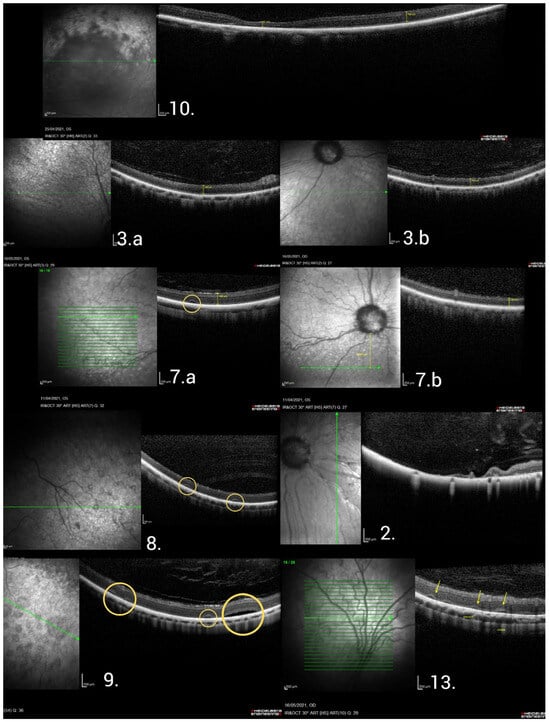

| 2. | M | 3 | 3 | 32 |

| 3. | M | 3 | 3 | 36 |

| 7. | M | 3 | 3 | 15 |

| 8. | M | 3 | 4 | 8 |

| 9. | F | 3 | 4 | 8 |

| 10. | M | 3 | 4 | 13 |

| 13. | F | 2 | 2 | 4 |